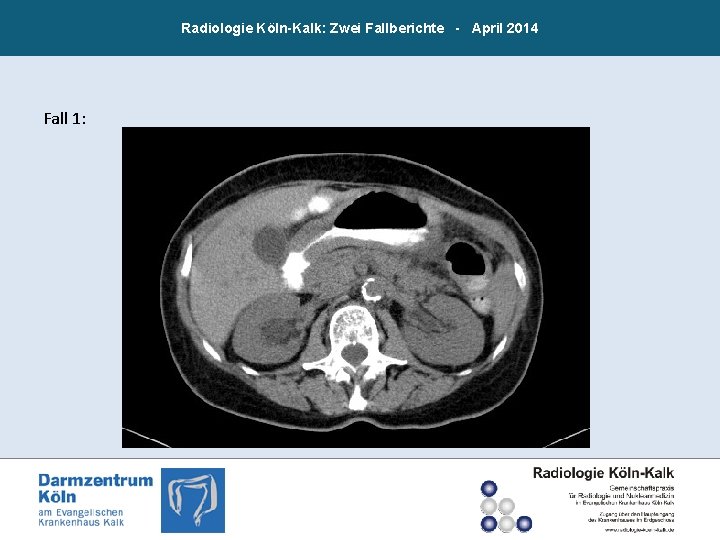

Radiologie Köln-Kalk: Zwei Fallberichte - April 2014 Fall 1: 78 jährige Patientin mit Haut- und Vulvametastasen eines invasivlobulären Mammakarzinoms; CT-Abdomen zum Staging: Auffällige Situation im Bereich von Magen und Kolonrahmen. Zeichen der Peritonealkarzinose.